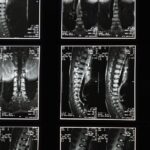

Avant de reprendre toute forme d’exercice, il est crucial d’évaluer la gravité de la dégénérescence discale en consultant un professionnel de la santé. Des tests d’imagerie comme l’IRM ou la radiographie peuvent être nécessaires pour déterminer l’étendue des dommages. Une évaluation complète permettra de définir des limites d’activité appropriées et de prévenir les aggravations de la condition.

Une IRM ou une radiographie est souvent utilisée pour confirmer le diagnostic d’un pincement discal ou d’un disque écrasé.

Une IRM ou une radiographie est souvent recommandée pour évaluer l’état de la colonne vertébrale.